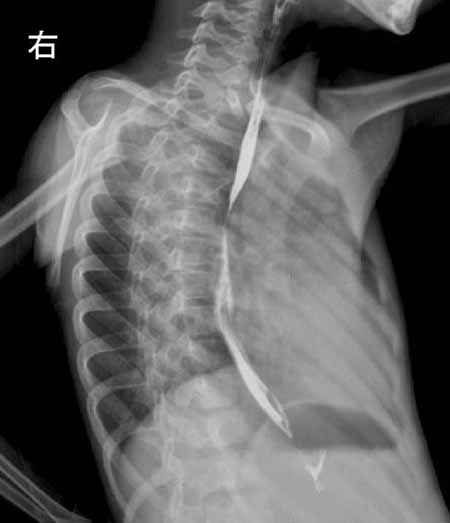

x线特点:主动脉型心脏,左室增大为主,主动脉增宽;肺动脉增粗。

结果收到,大家都没有猜对,法四学习了!肺内出现粗乱血管影或中下肺野及肺门附近有网状血管纹理,为体动脉侧支循环的表现,提示中度肺动脉狭窄。